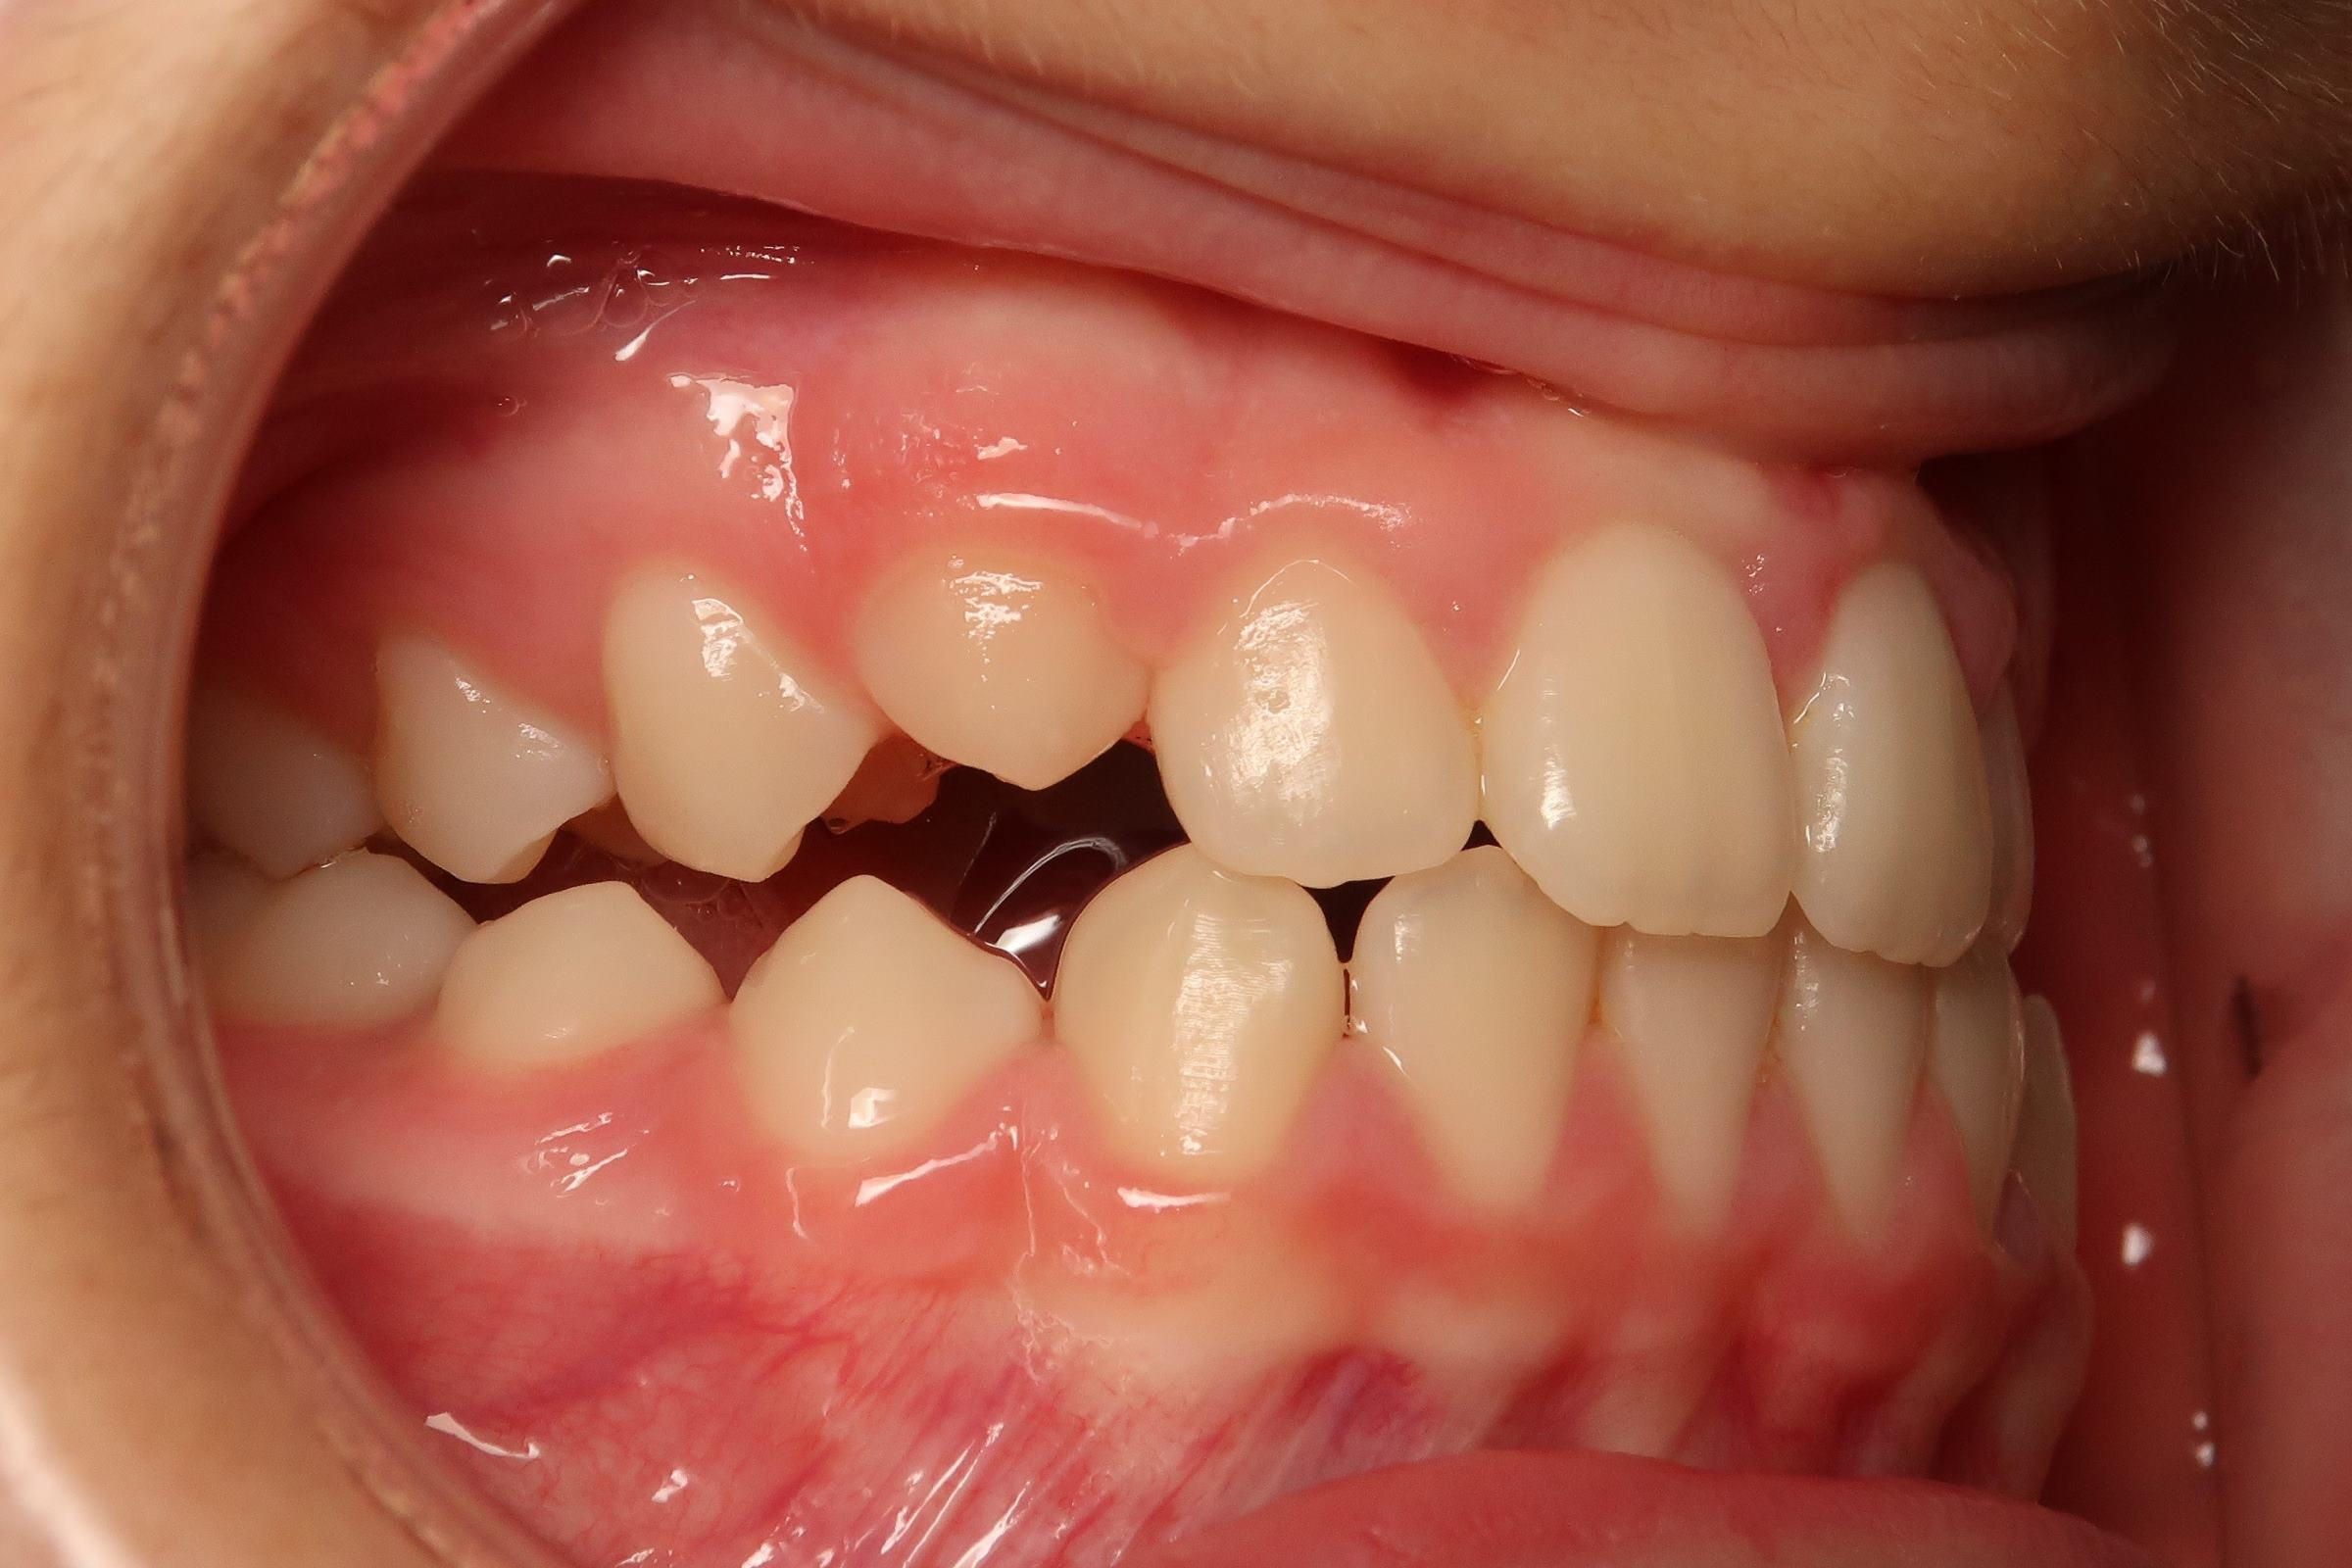

25. bout à bout anterieur 6 ans

dents du haut bout à bout par rapport à celle du bas

bilan début et en cours de traitement